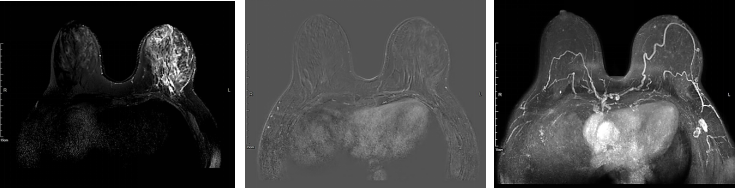

图5.新辅助治疗2周期后的乳腺彩超评估

图6新辅助治疗6周期后的乳腺彩超评估

图7.新辅助治疗2周期后的乳腺增强MRI评估

图8.新辅助治疗6周期后的乳腺增强MRI评估

患者自第3周期新辅助治疗起,正处于3~6月间上海新冠疫情封控时期,对影像学评估造成了较大的影响。根据ESMO新冠期间乳腺癌诊治临床处理优先原则,对于HER2+乳腺癌的新辅助/辅助治疗作为优先实施治疗,而对于新辅助治疗临床缓解的患者的影像学评估可以适当延后。因此,对于该患者4个周期后的影像学评估没有实施。

新辅助治疗6周期后再次CT评估,提示两肺未见明显异常密度影。纵隔内未见确切肿大淋巴结。双乳腺体致密,左乳局部可见点状高密度影,未见确切异常强化灶;双侧腋窝未见明显肿大淋巴结(图9)。

图9.新辅助治疗6周期后胸部CT平扫(箭头处提示金属clip位置)

临床疗效评估为PR。